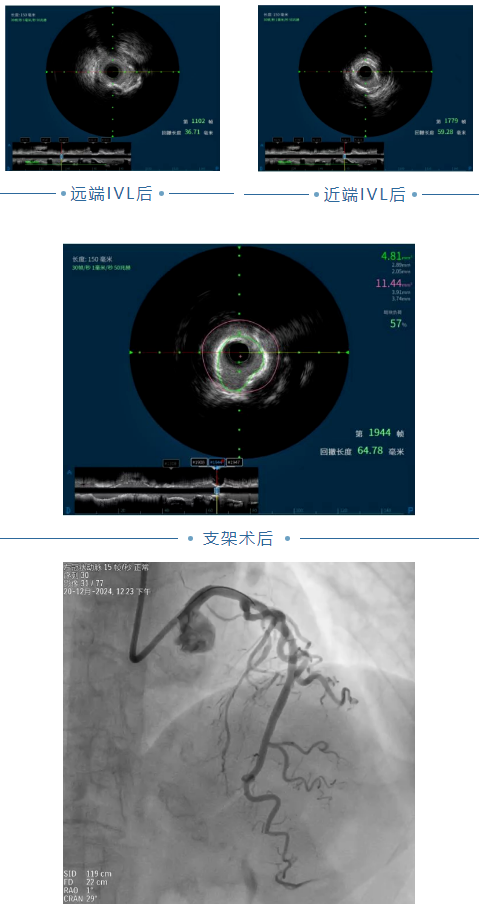

血管內(nèi)超聲IVUS檢查結(jié)果示:LAD長(zhǎng)病變,全程纖維斑塊為主合并360°環(huán)形鈣化,最小管腔面積 2.11mm2,狹窄83%。

將2.0×15mm預(yù)擴(kuò)張球囊送至LAD病變位置,由遠(yuǎn)及近分次擴(kuò)張,采用樂(lè)普2.75×12mm冠脈內(nèi)沖擊波導(dǎo)管對(duì)LAD近中段鈣化病變進(jìn)行沖擊波球囊導(dǎo)管冠脈腔內(nèi)成型預(yù)處理,先后共重復(fù)8個(gè)周期冠脈內(nèi)脈沖波治療;沖擊波球囊預(yù)處理后復(fù)查造影示LAD近中段病變較前明顯改善,鈣化環(huán)被打開(kāi),病變預(yù)處理充分,可進(jìn)一步行PCI治療,遂分別將雅培2.75×38mm.3.0×33mm冠脈支架送至LAD血管病變位置處釋放由遠(yuǎn)及近分別釋放,再分別以2.75×15mm、3.0×15mm后擴(kuò)張球囊充分?jǐn)U張支架。復(fù)查IVUS示術(shù)后支架貼壁良好,無(wú)夾層血腫形成,最小管腔面積4.81mm2,殘余狹窄57%;復(fù)查造影示LAD近中段長(zhǎng)病變消失,TIMI血流III級(jí)。